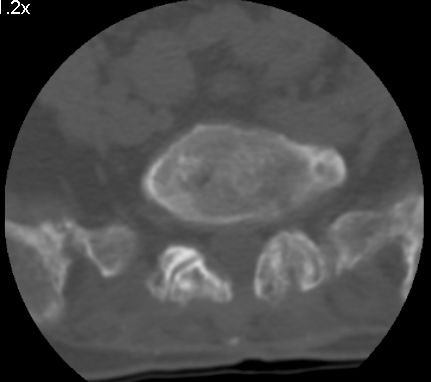

以下是引用余辉在2007-9-4 21:00:00的发言:[br]椎体棘突有点异常(像是被切割了),不知有否手术史,如椎体融合术等。单纯的退行性变可以出现椎间隙变窄,但同时一般会出现椎体上下缘的硬化增生,且椎体间完全融合的机率更小,本例椎体完全融合且椎体上下皮质缘破坏掉了,如果没有手术史,就应该考虑椎间盘炎性病变了,且椎体棘突及棘间韧带的变化也并不是不支持这个,多数小关节也融合了,且其形态也容易让人联想到如强脊炎及类风关等病变。[br][br][本贴已被 余辉 于 2007-9-4 21:03:55 修改过]

以下是引用chry3在2007-9-4 20:42:00的发言:[br]椎间盘病史?是什么样的病史,无双下肢放射痛,那就不是椎间盘突出了。是感染、什么性质的?[br]从图象看椎间隙消失,椎间盘组织未见,锥体滑脱是因为椎间盘溶解造成的[br]l4、5椎体骨质结构未见异常,l5上缘是l4的长期压迫所致[br]还是考虑椎间盘感染,结核。[br]